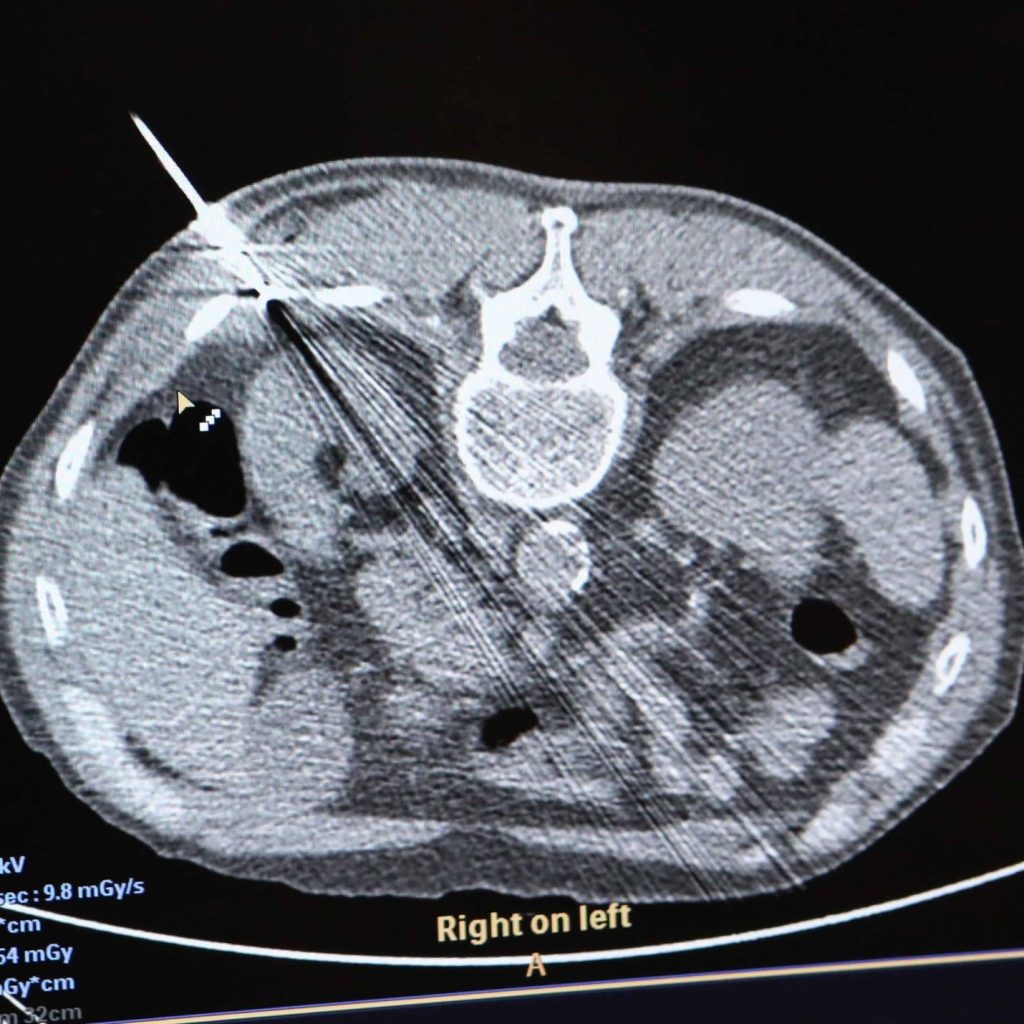

Prvú kryoabláciu v UNLP realizoval MUDr. Viliam Weis: „Pacient mal nádor na obličke s veľkosťou dva centimetre, bol to ideálny prípad vhodný na tento pokrokový a bezpečný postup liečby. Priamo do nádoru sme pod CT kontrolou zaviedli dve kryoihly a vykonali kompletnú abláciu. Benefitom pre pacienta bola lokálna anestézia, aj preto ho čaká rýchlejšia rekonvalescencia, skorší návrat domov a menšie riziko komplikácií.“

Funguje na princípe hlbokého mrazenia za pomoci argónu, ktorý pri cirkulácii a rozpínaní v kryoablačnej ihle vytvára chlad. V okolí kryoablačnej ihly je teplota až -140°C, postupne vzniká ľadová guľa, ktorá dosahuje – 40°C, tá obklopí nádor a zabezpečí jeho kompletné odumretie. „Kryoablačný prístroj je napojený na argónové bomby, kde je na 300 bar stlačený argón, ktorý v kryoablačných ihlách generuje chlad. Kryosondy (ihly) sa pod CT kontrolou zavedú priamo do nádoru, nádorové tkanivo sa zmrazí, čím dôjde k deštrukcii nádorového ložiska a časť zdravého parenchýmu ostane zachovaná. Ak sú kontrolné vyšetrenia v poriadku, pacient môže ísť na druhý deň domov,“ vysvetlil prednosta kliniky MUDr. Piotr Pedowski, MPH. „Po aplikácii argónu sa zvyčajne do niekoľkých dní vytvorí jazvové tkanivo, ktoré postupne nahradí zničené rakovinové bunky.“